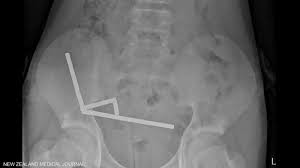

ووفقًا لتقرير نُشر في المجلة الطبية النيوزيلندية، وصل المراهق — الذي لم يُكشف عن هويته — إلى مستشفى تاورانغا في الجزيرة الشمالية بعد معاناته من آلام شديدة بالبطن استمرت أربعة أيام. وخلال الفحص، اعترف بابتلاعه ما بين 80 إلى 100 قطعة مغناطيسية قبل أسبوع من دخوله المستشفى.

وأظهرت الفحوص الطبية أن هذه القطع تنتمي إلى نوع من المغناطيسات الصغيرة المحظورة في نيوزيلندا منذ عام 2013، حيث تسببت في التصاق أجزاء من الأمعاء الدقيقة والغليظة وتلف أنسجتها نتيجة الضغط المغناطيسي المستمر.

وخضع الطفل لعملية جراحية دقيقة استمرت عدة ساعات، تمكن الأطباء خلالها من إزالة المغناطيسات والأنسجة المتضررة بنجاح، قبل أن تستقر حالته ويُسمح له بمغادرة المستشفى بعد ثمانية أيام من المراقبة الدقيقة.